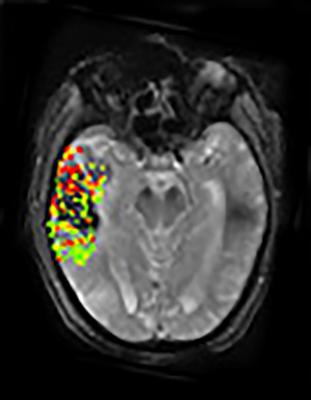

Using a new method of image processing, Leigh’s group was able to get detailed measurements on the extent to which the blood-brain barrier is disrupted following a stroke. Combining that data with findings from the DEFUSE-2 study revealed that large degrees of blood-brain barrier disruption were associated with severe bleeding following endovascular therapy. Extensive breakdown of the blood-brain barrier was associated with parenchymal hematoma, a form of bleeding in the brain that carries the greatest risk for the patient. In addition, the results showed a link between the location of blood-brain barrier damage and post-treatment brain bleeding.

According to the authors, examining blood-brain barrier disruption on brain images may potentially help doctors identify patients not likely to benefit from endovascular therapy. “It is too early to say how these images will be able to help guide clinical decisions, but they can expand how we think about stroke, especially as we try to broaden treatment options for this disease that can have devastating consequences,” said Leigh.